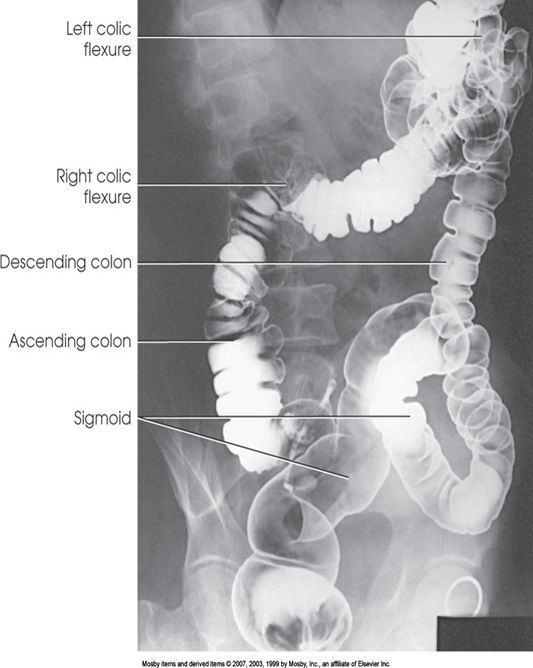

左後斜位(LPO)

胃底部充滿鋇劑。

體部、幽門充滿空氣。

十二指腸球部偶爾會充滿空氣。